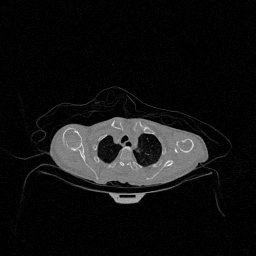

The results for simulated noisy data are shown in Fig. 2. The first and third rows display two representative slices from the test set, and the second and fourth rows present the corresponding error maps. The traditional WCE method suppresses cupping artifacts and recovers some missing anatomical structures but still shows noticeable deviations from the ground truth. Predictions from the four diffusion-based models demonstrate a markedly improved ability to restore anatomical structures. Among them, cDDPM fails to fully reconstruct the patient bed and retains residual noise in its outputs. This noise is attributable to an incomplete reverse denoising process rather than residual Poisson noise, as evidenced in our noise-free experiments (Fig. 5 in the Appendix). PatchDiffusion, diffusionGAN, and I2SB achieve similar visual quality, with I2SB producing the cleanest and most consistent reconstructions.

The experimental results on clinical head data are shown in Fig. 4. The reference images were reconstructed using the fast iterative shrinkage-thresholding algorithm (FISTA) with total variation regularization from non-truncated projection data. In the WCE reconstructions (Fig. 4(b)), severe truncation prevents accurate recovery of anatomical structures outside the FOV. Despite being trained solely on simulated data with a domain gap, all deep learning models can restore a substantial portion of the missing anatomy. Among them, the diffusion-based methods recover soft-tissue boundaries more faithfully than the conventional deep learning approach FBPConvNet, highlighting their stronger image generation capability. However, cDDPM reconstructions exhibit more noticeable noise than those from other methods, consistent with the simulated data results. The patchDiffusion model introduces artifacts within the FOV, likely due to its patch-wise processing strategy. While I2SB shares the same limitations as other diffusion models in perfectly restoring soft-tissue detail, it produces fewer residual noise patterns and fewer artifacts within the FOV boundaries. Overall, Fig. 4 demonstrates the strong efficacy of I2SB in reconstructing real CBCT data.